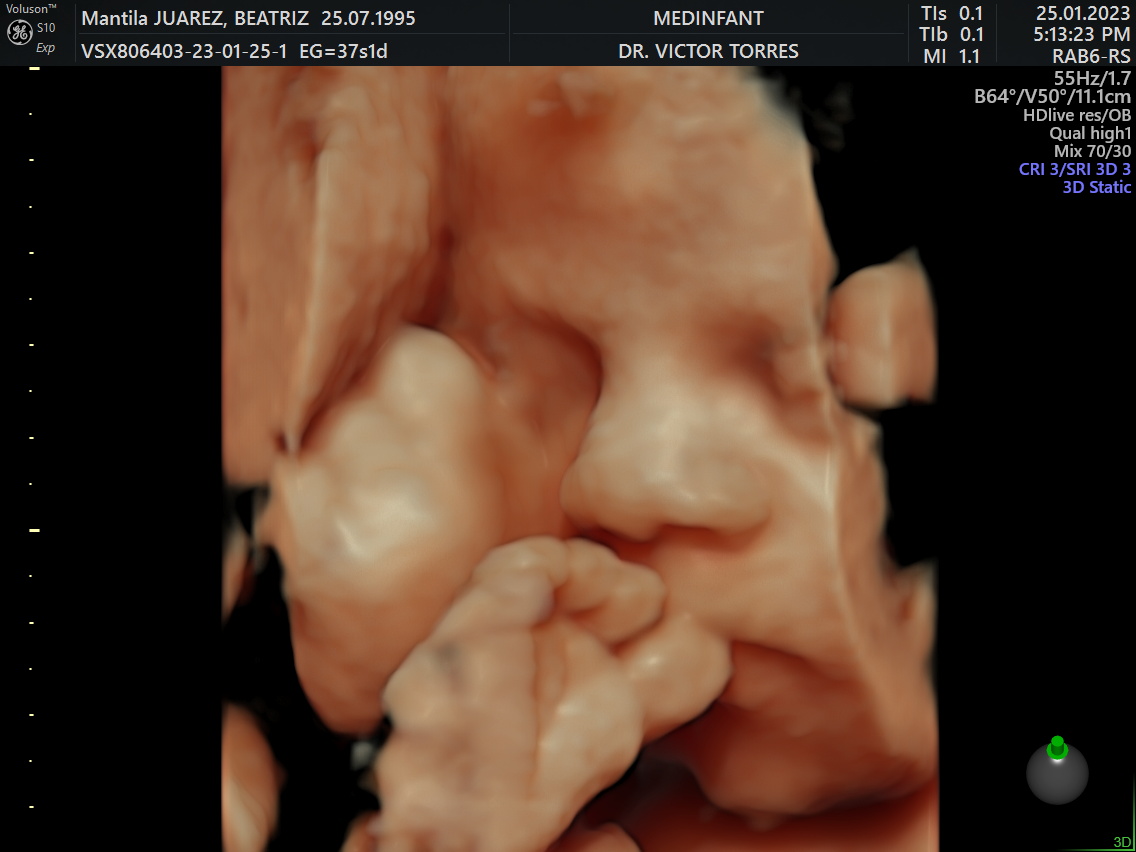

Dr. Victor Torres C.

Ginecólogo-Obstetra | Medicina Fetal

• Posgrado en Medicina Fetal por Fetal i+D Education Barcelona.

• Fellow en Cardiología Fetal por la Fundación Internacional de Medicina Materno Fetal.

• Más de 10 años de experiencia en el cuidado de la salud femenina y materno-fetal.

• Entrenamiento en Ginecología Laparoscópica, Ecografía Gineco-Obstétrica y Cuidados Intensivos Maternos en centros de referencia en Perú y México.

• Auditado y con licencias por The Fetal Medicine Foundation.

Galería